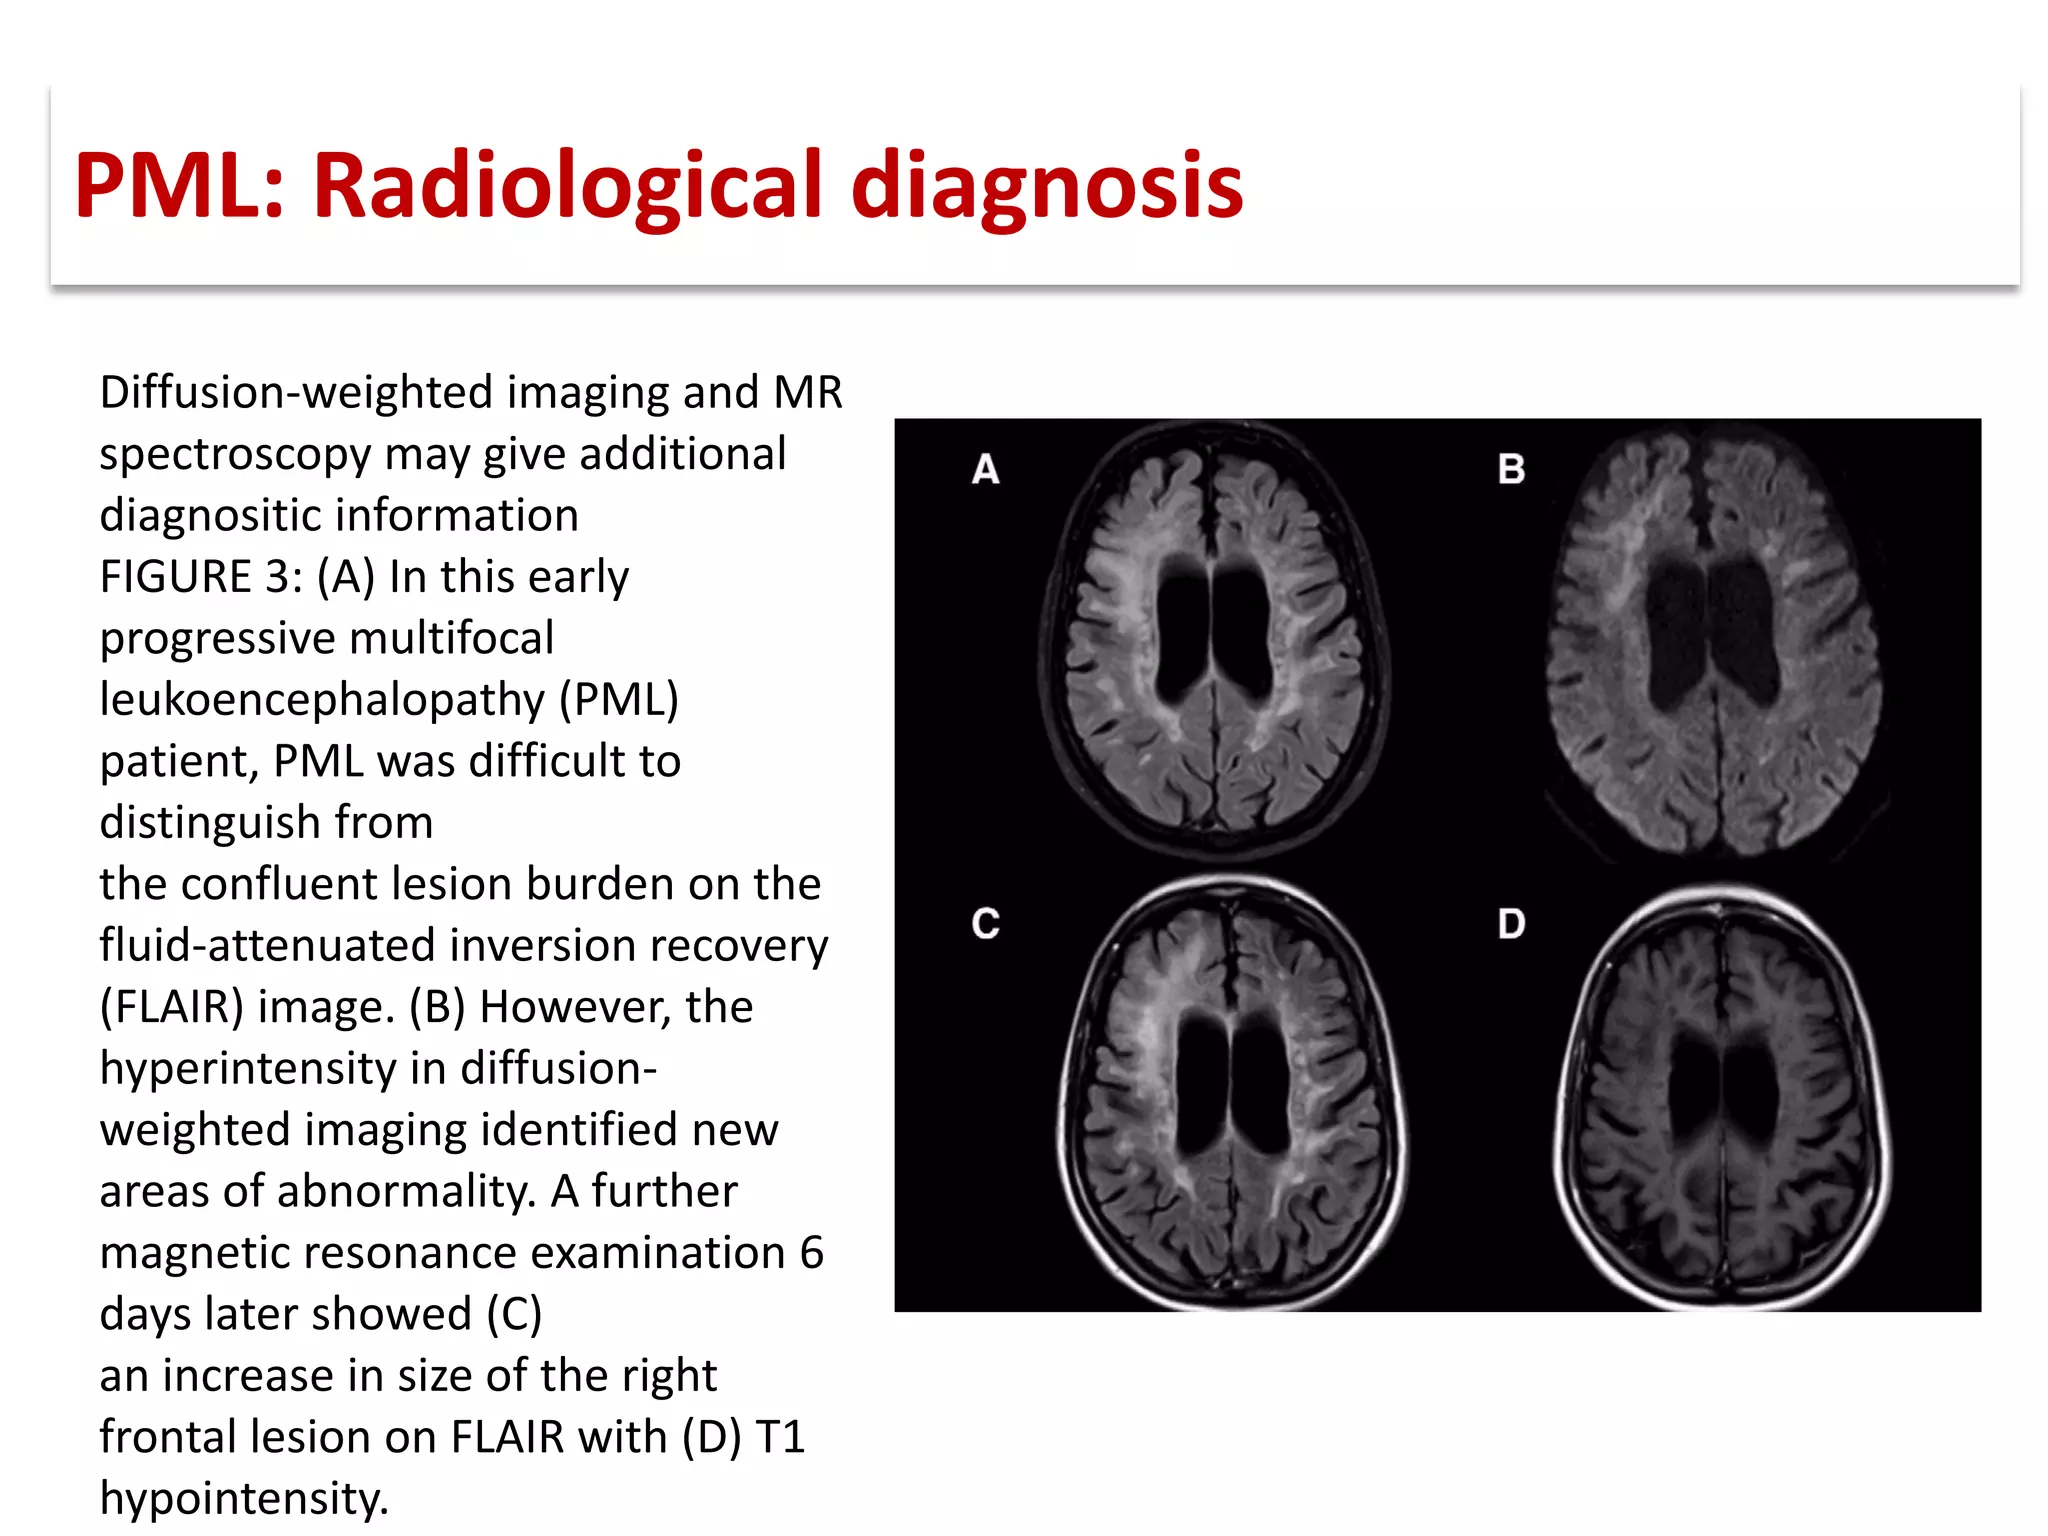

This document discusses progressive multifocal leukoencephalopathy (PML), an opportunistic infection caused by the John Cunningham virus (JCV) that leads to demyelination in the central nervous system. It highlights the epidemiology, clinical manifestations, diagnostic methods, and risk factors associated with PML, particularly in immunocompromised patients and those undergoing immunomodulatory therapies. It also presents data on the incidence of PML in patients treated with natalizumab and other therapies, addressing the relationships between these treatments and the development of PML.